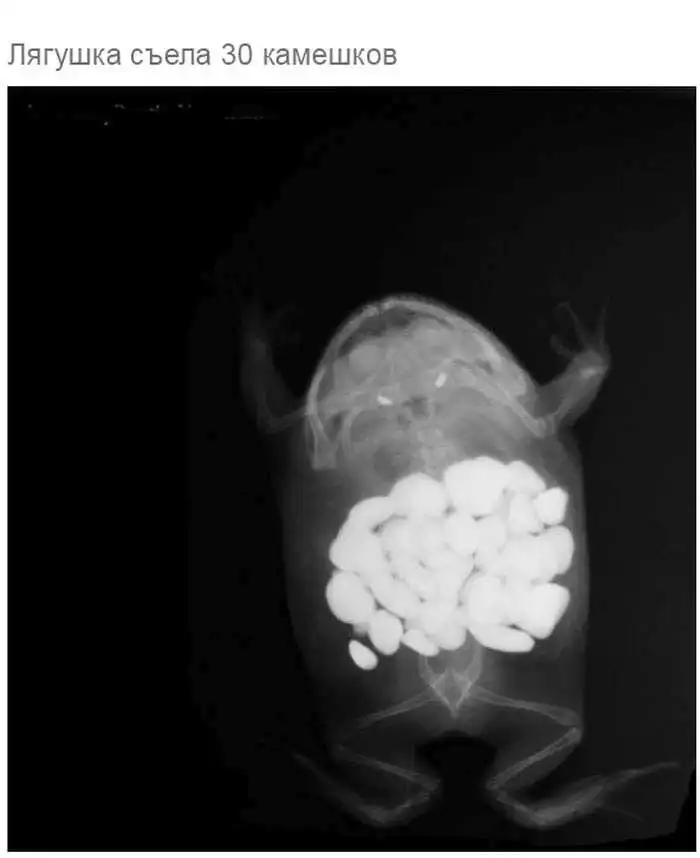

Что может оказаться в желудке собаки

Думаю, всем собачникам известно, что порой у собак бывают такие заскоки, когда они в прямом смысле слова жрут все подряд.